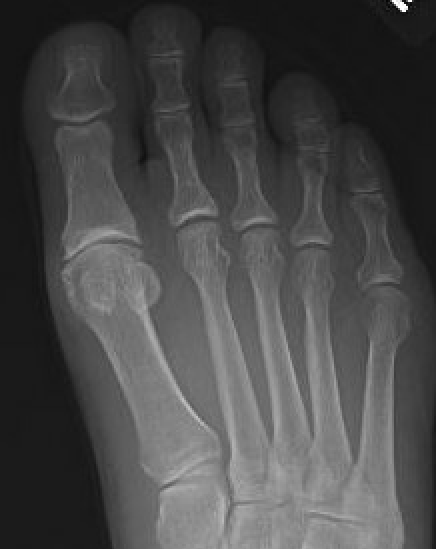

X-ray

Osteoarthritis

- joint space narrowing

- dorsomedial osteophyte

Mild to moderate OA